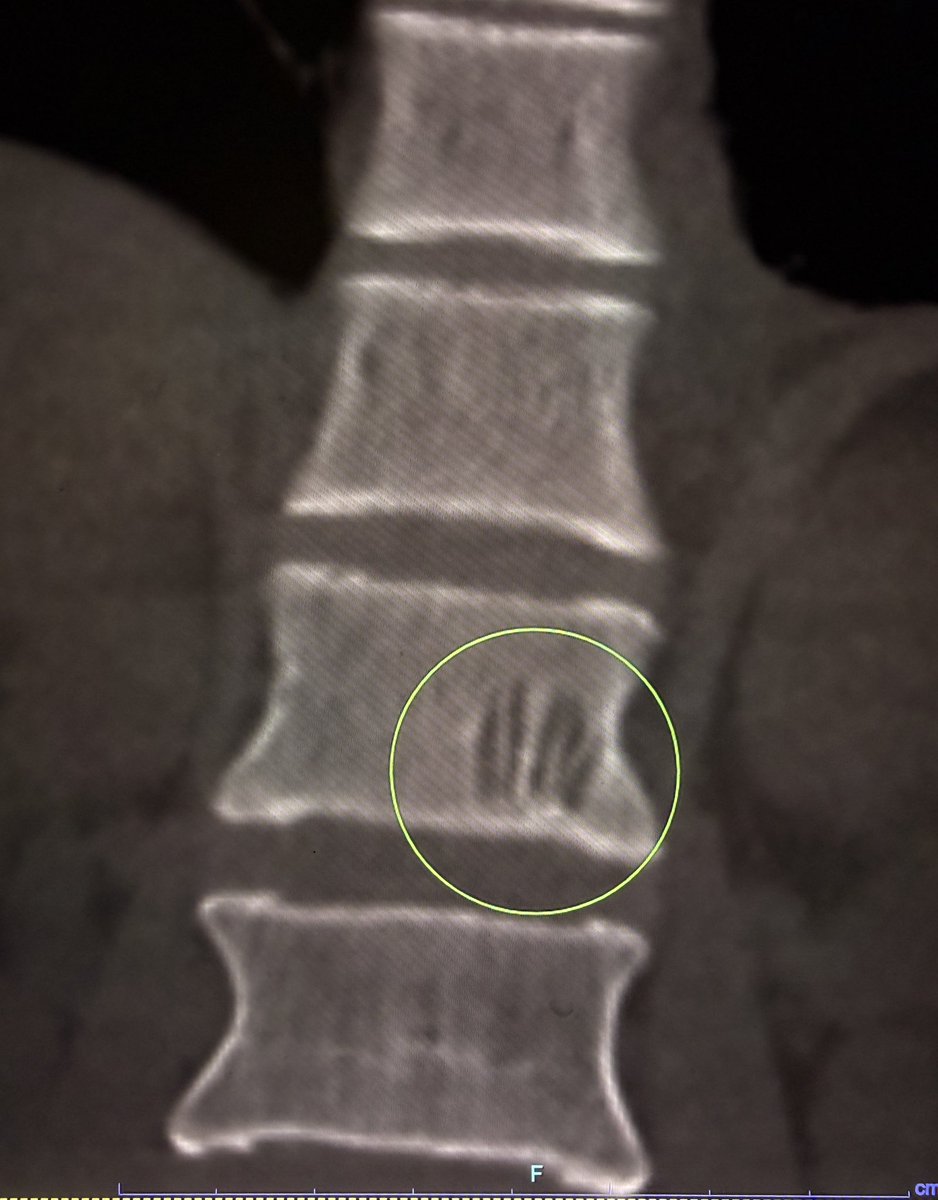

Are Most Rotator Cuff Tears Actually Tears?

If you have a rotator cuff tear on an MRI report, almost everything you have been told about it is more wrong than right.

A short thread on what the cuff actually is, why most "tears" aren't what you think, and why surgery is rarely the right first step.